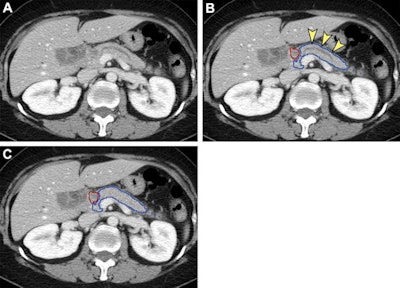

To see if AI could help, the researchers developed an end-to-end, deep learning-based tool that comprises a convolutional neural network (CNN) for segmenting the pancreas on CT and then an ensemble of five CNNs to detect pancreatic cancer. After producing 89.9% sensitivity and 95.9% specificity on an internal test set of 256 patients, the model was then applied to an external test set of 1,473 CT studies gathered from institutions throughout Taiwan.

Interestingly, the algorithm also correctly identified pancreatic cancer in two cases by analyzing only the nontumorous portion of the pancreas.

"Our results also suggest that the classification convolutional neural networks might have learned the secondary signs of [pancreatic cancer], which warrants further investigation," the authors wrote.

The tool can also speed up radiologist interpretations by highlighting the suspicious region of interest, Wang said in a statement from the RSNA.